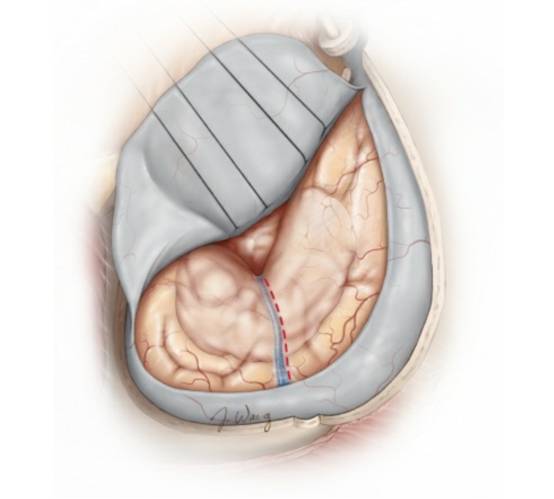

在完成上述步骤后,笔者会新月形切开硬脑膜,分离前侧裂,以暴露脑膜瘤。

图7. 左侧扩大翼点开颅,切除床突后暴露肿瘤组织。在该病例中,大肿瘤由侧裂向外侧延伸。通过腰大池缓慢释放约40ml脑脊液后(每次释放10ml),可将肿瘤从蝶骨翼硬脑膜外侧游离出来,并电凝其内侧的硬脑膜附着点。该操作是手术中非常关键的一步,通过彻底阻断肿瘤血供,从而避免频繁的止血操作,加快后续的肿瘤切除过程。

图8. 笔者会沿着前颅窝继续阻断肿瘤血供,同时需注意视神经的大致位置,以避免热损伤的发生。脑脊液引流,侧裂分离和吸引器的合理使用,可避免使用固定脑牵开器。